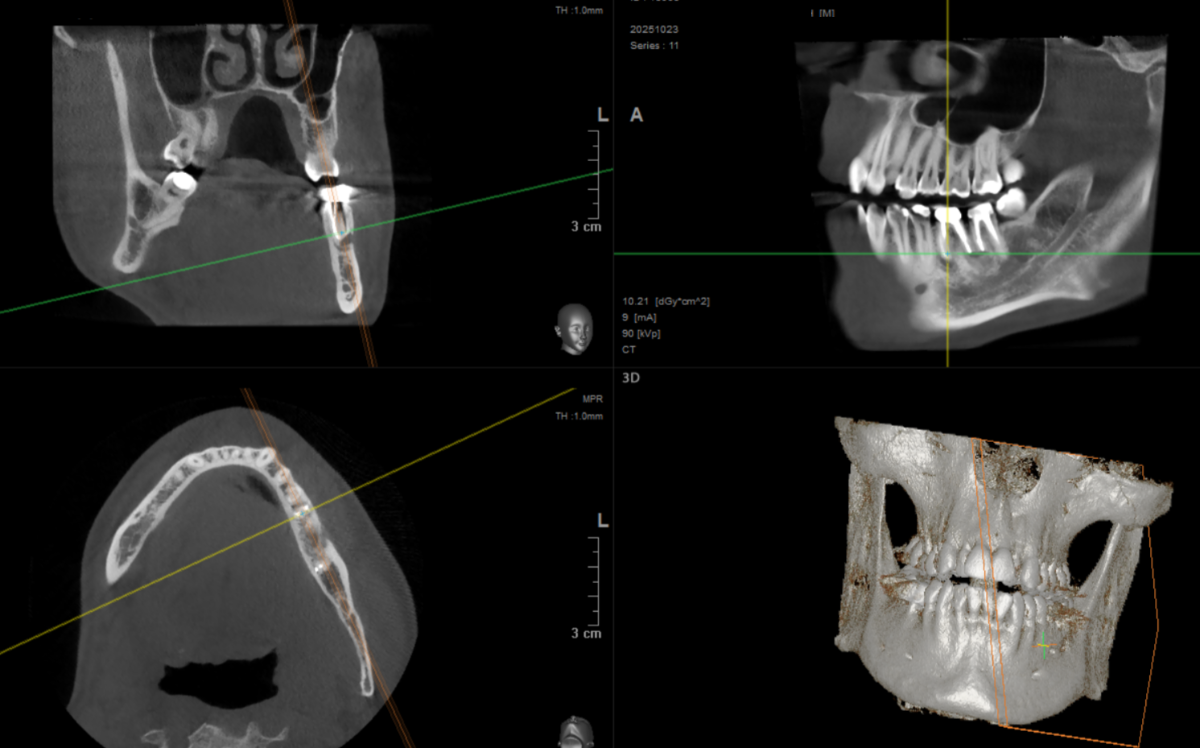

artek Опубликовано 16 декабря, 2020 Поделиться Опубликовано 16 декабря, 2020 Здравствуйте, товарищи! Почти год назад переличил 2 зуба под микроскопом, как мне рекомендовали в данной теме на форуме.Каналы были перелечены, поставлены временные коронки.Сейчас сделал КТ, врач говорит, что какой то явной динамики по основной кисте не наблюдается. То есть она ощутимо не уменьшилась и не увеличилась.Вот срезы до и послеЭти зубы ощутимо не беспокоят, изредка бывает несильные тянущие боли, скорее дискомфорт.Врач предлагает закрыть зубы постоянными коронками. Хотя вкладываться в коронки, не имея выраженной позитивной динамики, как то не очень хочется.Собственно вопрос, что порекомендуете дальше делать? Какие возможны варианты? Ссылка на комментарий

artek Опубликовано 5 марта, 2022 Автор Поделиться Опубликовано 5 марта, 2022 Здравствуйте. Прошел еще год с лишним после последнего КТ(снимок выкладывал выше), сделал новое КТ(прикрепил срезы). Собственно вопрос, что порекомендуете делать? Вроде как временные коронки уже 2 года стоят(срок годности истек) и нужно менять на постоянные, но и явной динамики по уменьшению кисты я лично не наблюдаю....Как быть? Ссылка на комментарий